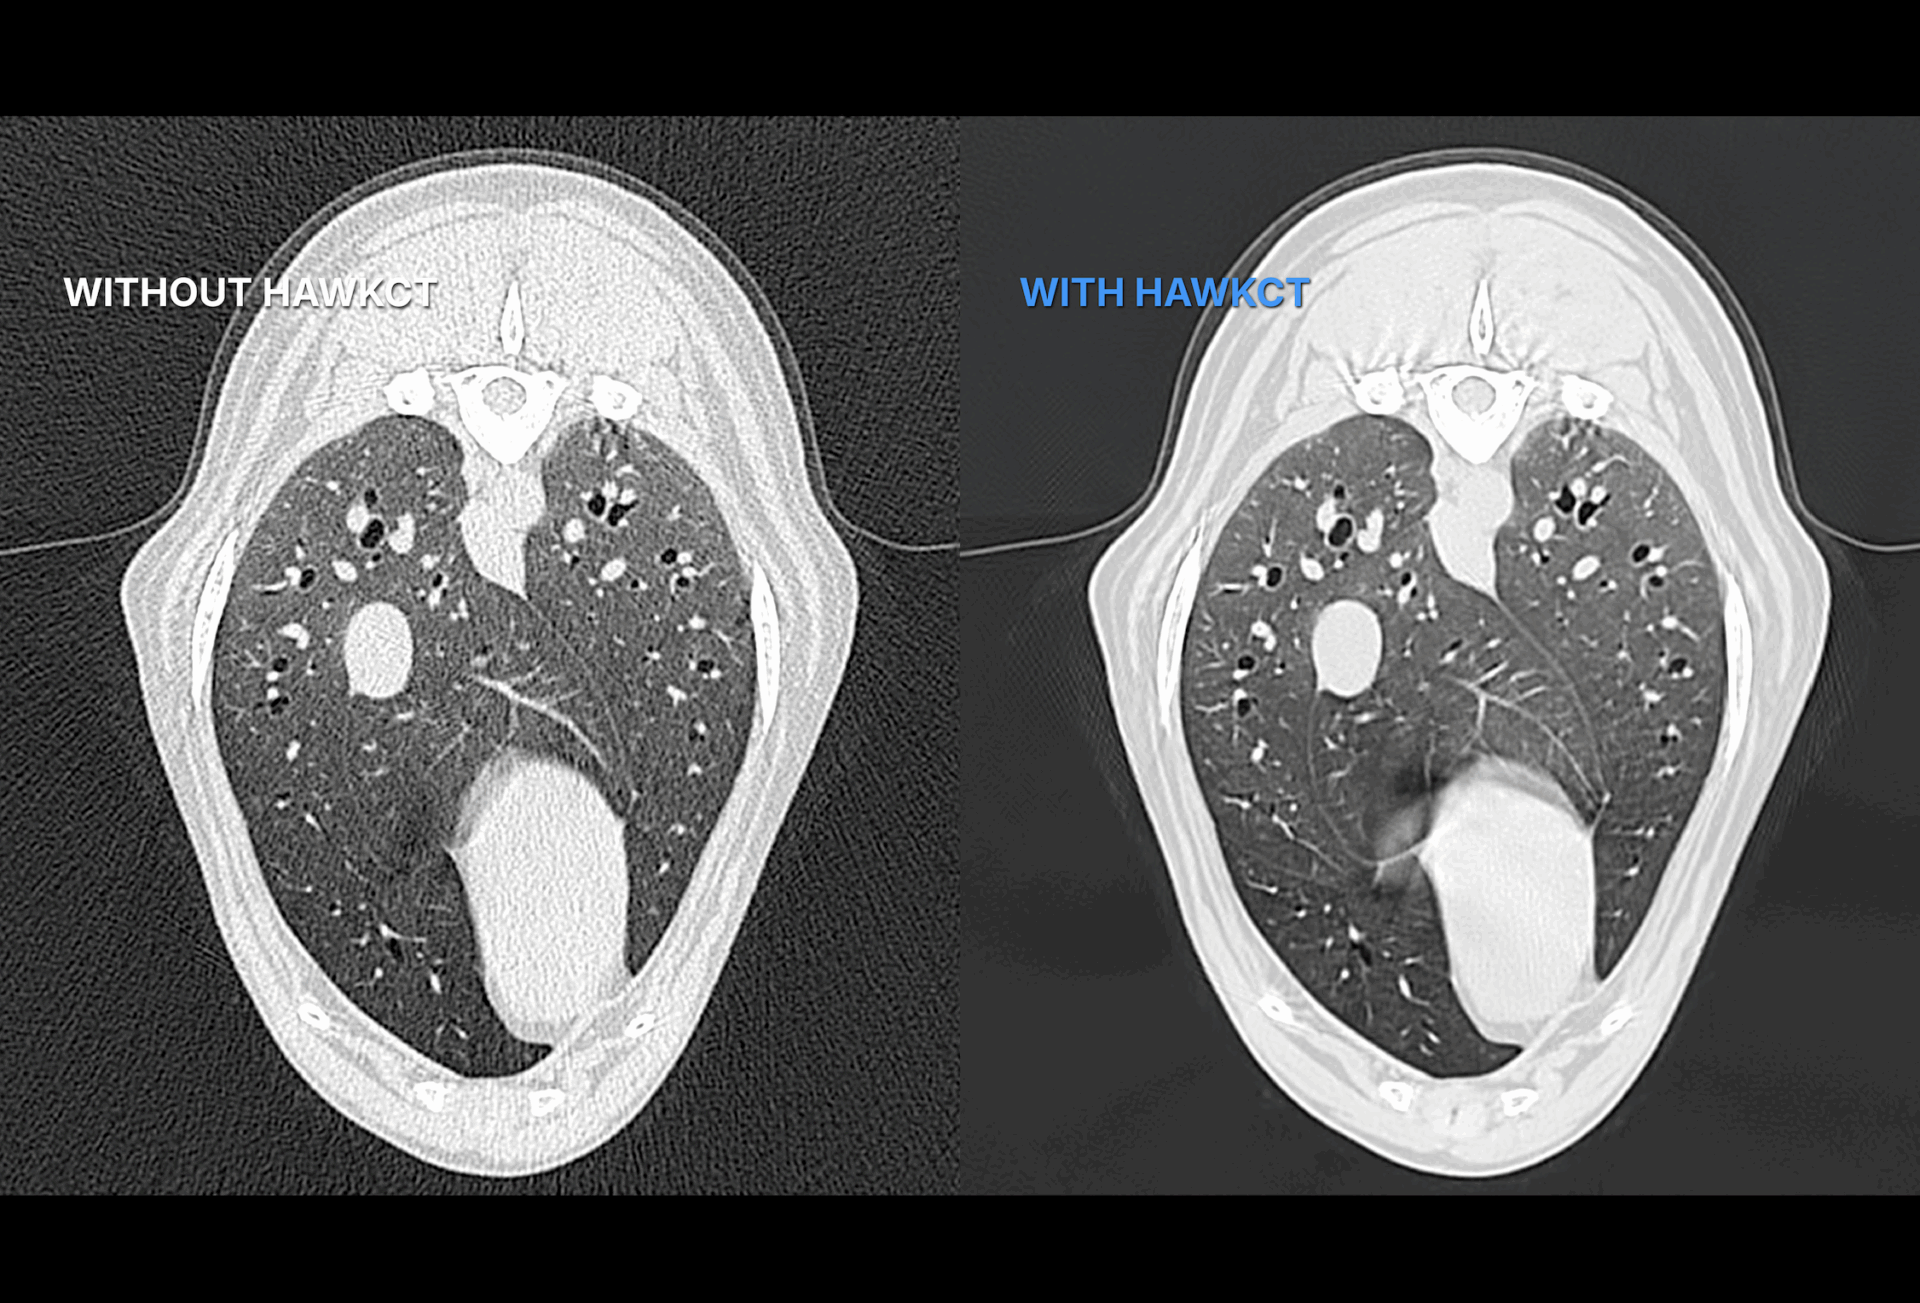

HawkCT is a veterinary CT deep learning algorithm designed to define a new standard in imaging. It delivers faster scans, reduced radiation exposure, and sharper image quality.

HawkCT optimizes workflows, lowers energy and consumable costs, and integrates seamlessly with any CT system. By cutting anesthesia time and reducing radiation dose, it improves patient safety while maintaining diagnostic precision. Its advanced reconstruction enhances contrast and resolution, providing consistent image quality across all sequences. Exclusively built for veterinarians, trained and validated on animal data, HawkCT empowers clinics with faster, safer, and more sustainable CT imaging.